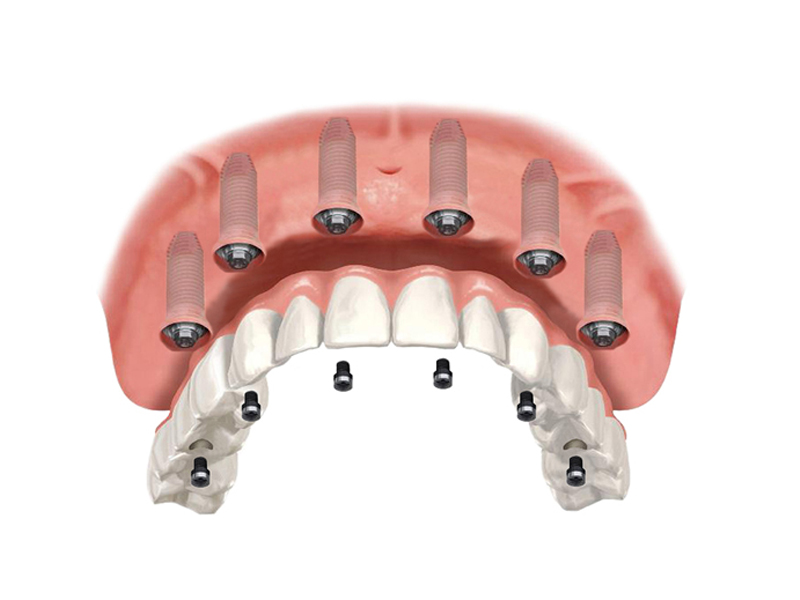

8 dental implants

8 abutments

The All on 8 dental implant system consists of positioning 8 dental implants per dental arch, functioning as "anchors" for a fixed and non-removable dental bridge. This system is recommended in cases where the patient has lost more than 80% of his natural teeth.

These dental implants will support a fixed dental bridge (permanently cemented on the implants) between 12 and 14 units (teeth). Before receiving All-on-8, the patient must have enough bone to support the implants. If there is not enough bone, a bone graft is needed. An All-on-8 requires more bone and more bone strength than an All-on-4.